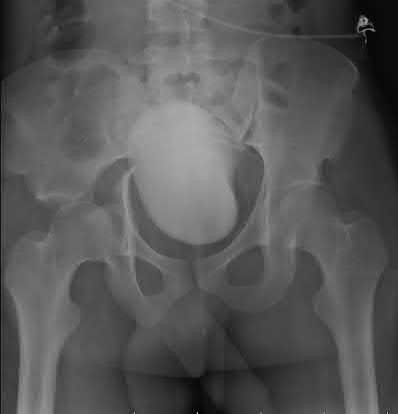

Question 11:

A poly-trauma patient presents hemodynamically unstable with an anteroposterior compression (APC-III) pelvic ring injury. A circumferential pelvic binder is requested to reduce pelvic volume and control hemorrhage. To be anatomically effective, the binder must be centered precisely over which of the following landmarks?

Correct Answer: Greater trochanters

Explanation:

For optimal mechanical advantage and effective reduction of an 'open book' pelvic fracture (APC type), a pelvic binder must be applied directly over the greater trochanters of the femurs. Applying it higher, such as over the iliac crests, is a common error that fails to adequately close the pelvic ring and can paradoxically open the true pelvis.